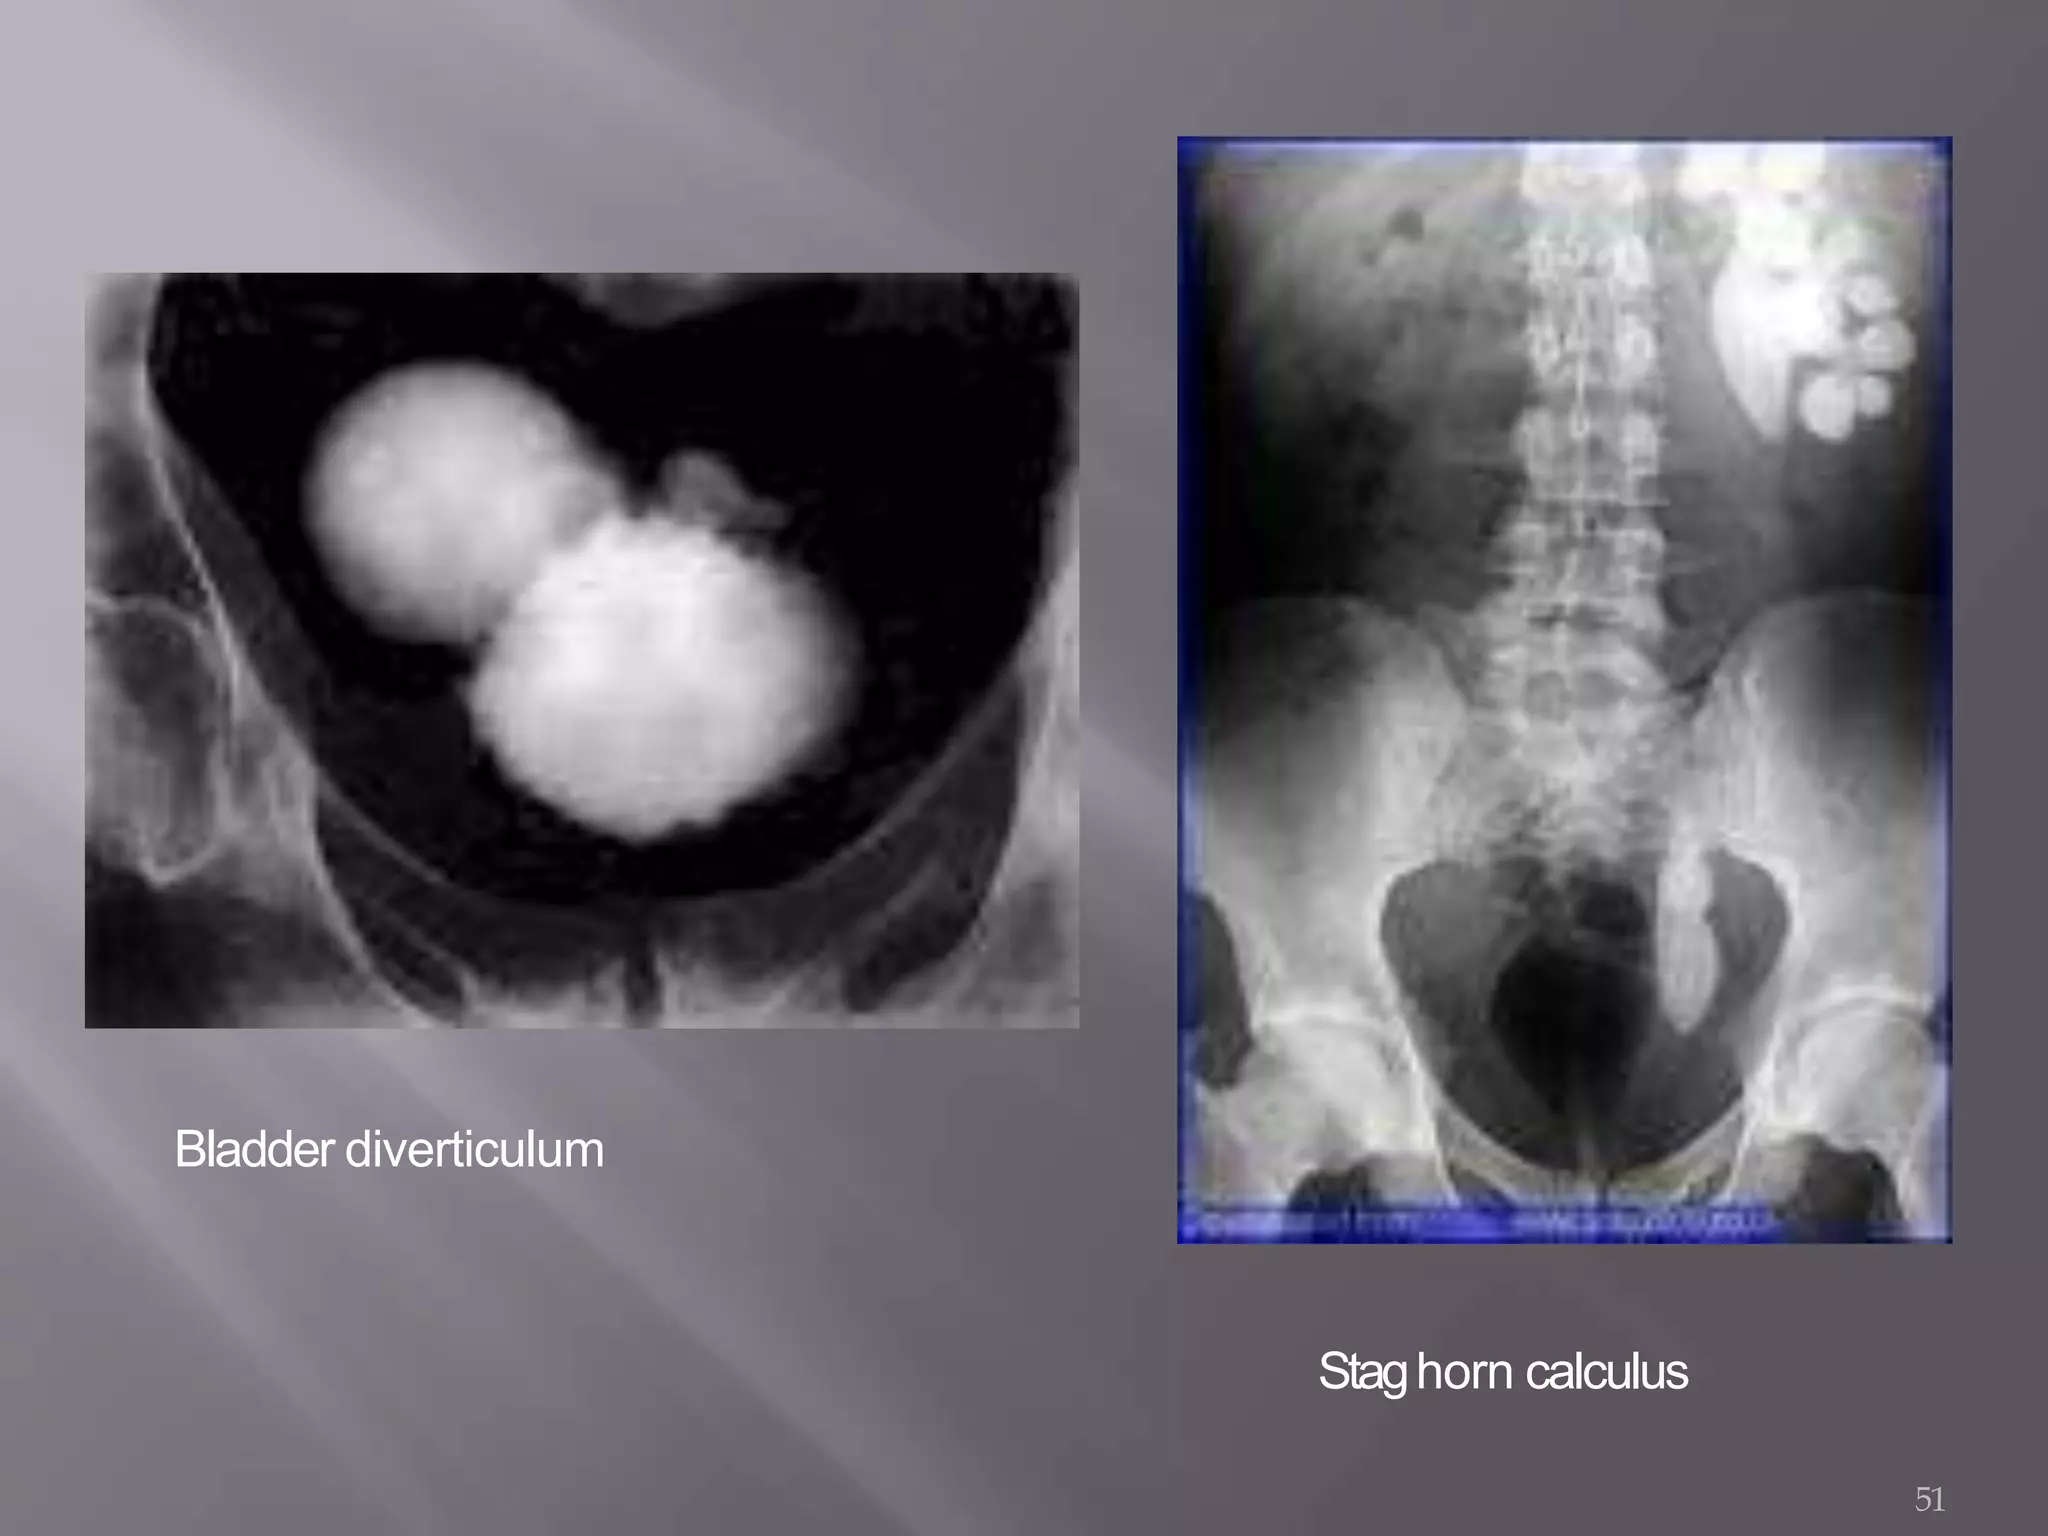

• Bladder diverticulum: Abnormal pouch formed withinbladder.

Lateral film of bladderarea.

Bladder diverticulum

51

Staghorn calculus